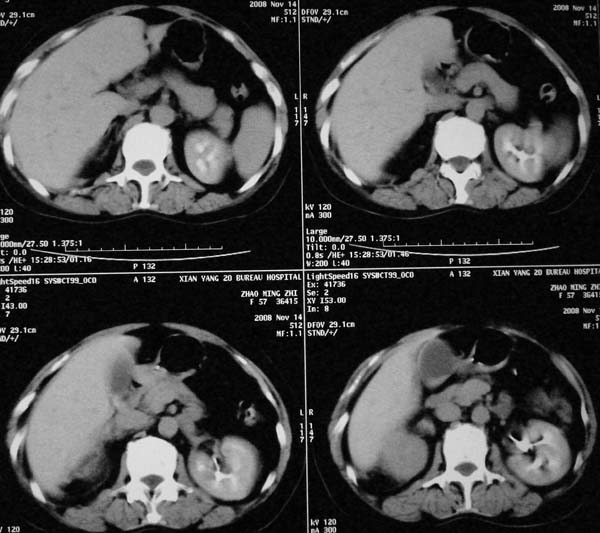

以下是引用dr.yang在2008-11-9 21:56:00的发言:[br]右肾上极占位?建议增强

以下是引用x-man在2008-11-9 22:30:00的发言:[br]建议先增强,右肾影明显增大,上极见边不清低密度肿块影,肿瘤待定.

以下是引用卜一在2008-11-10 8:09:00的发言:[br]建议先增强,右肾影明显增大,上极见边不清低密度肿块影,肿瘤待定.支持!另:第一次碎石是否肾受到损伤?合并感染?不知第一次碎石前是否做过彩超?

以下是引用dsl555在2008-11-9 23:57:00的发言:[br]建议先增强,右肾影明显增大,上极见边不清低密度肿块影,肿瘤待定. [br] [br]